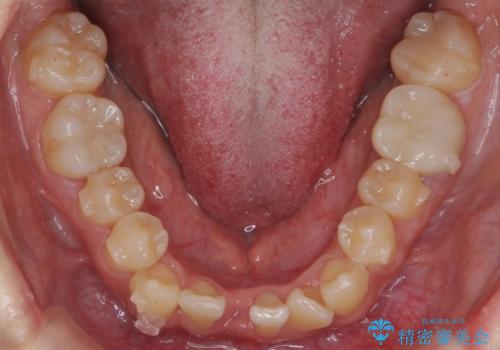

下の前歯のみ1本抜歯しています。

下の前歯の周りの骨は薄いことが多く、無理に並べると唇側の骨がやせて歯ぐきが下がり歯が長く見えます。

それを回避するために今回は下顎前歯を一本抜歯をしています。